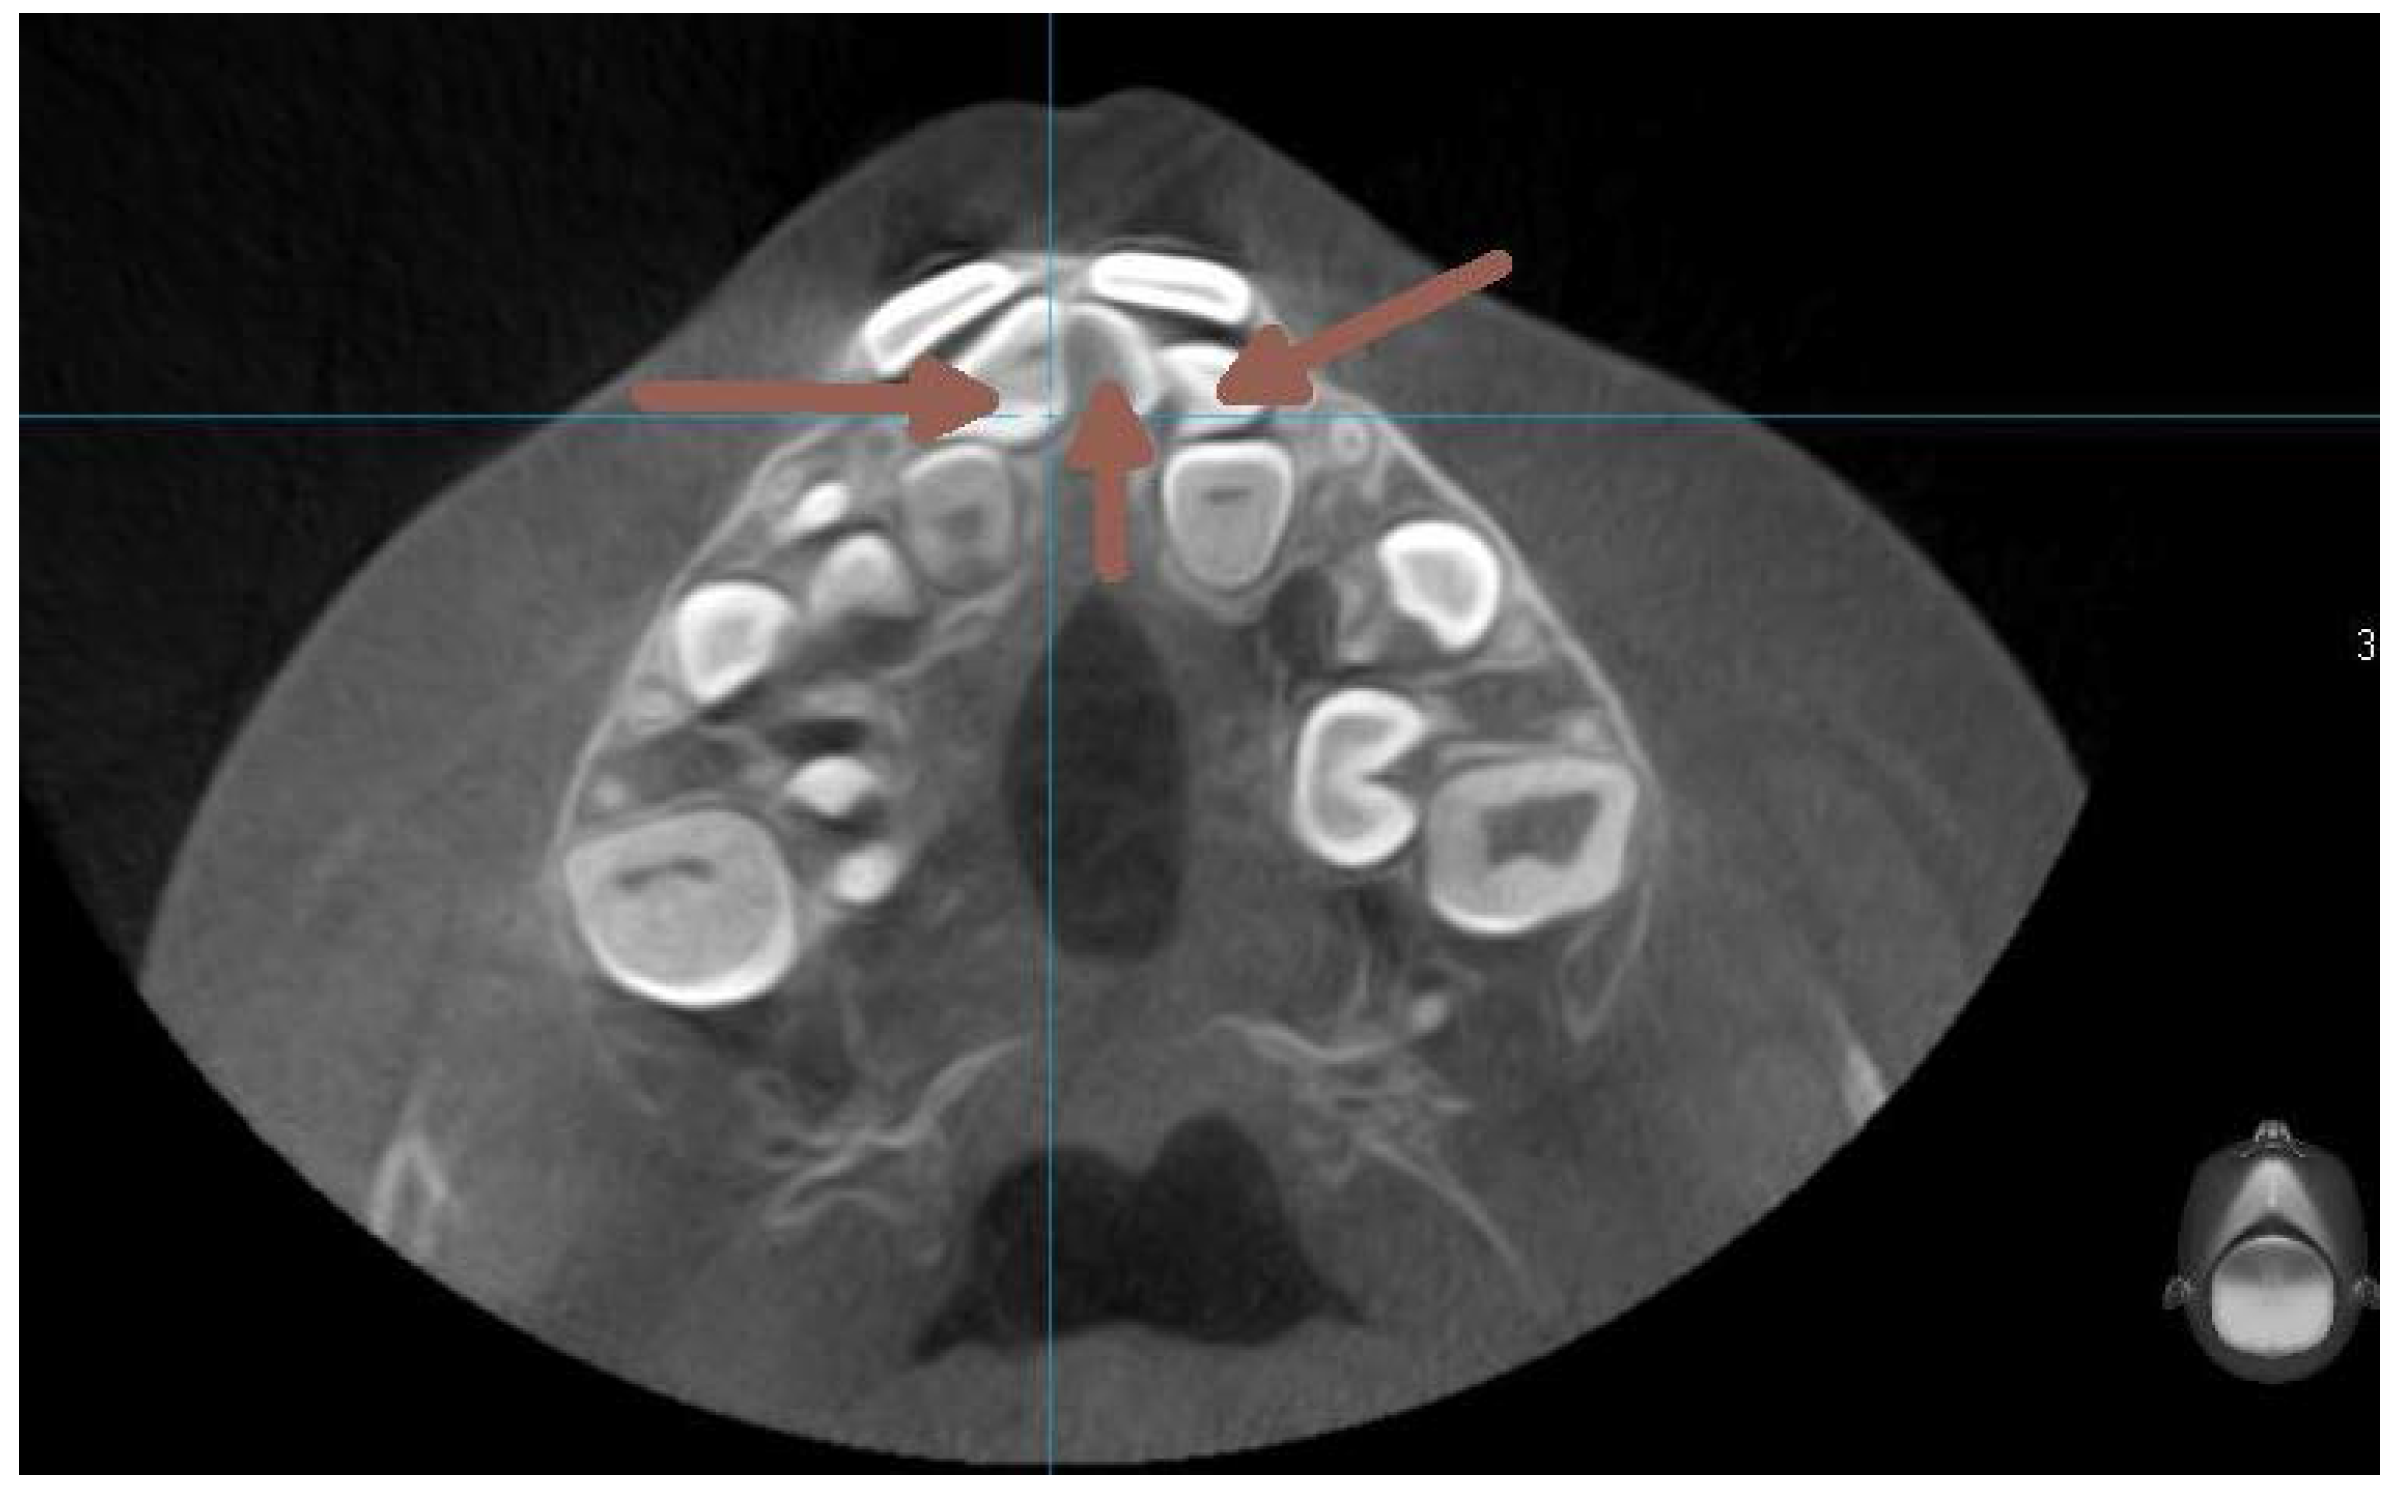

The next two OPG x-rays were taken after 11 months. On the latter (2017) (Figure 5) it became clear, that 22 and 11 were inhibited in eruption. ( DA 9,1 and 9,3, CA 12 y 11 mths) The patient was referred to the second CBCT scan image reproduction to make clear the underlying surgical situation. (Figure8). The CBCT scan revealed the position of supernumerary teeth also in the lower dental arch. (Figure 8.,9.)

Figure 9. The CBCT taken in 2017. Axial section on the level of premolars .

At this time the 33 and 43 were slowing down their eruption, therefore another surgical intervention was needed. Another CBCT scan image was necessary to prove the proximity of the crowns of the lower canines to the apical area of the lower lateral incisors. (Figure 15).

Figure 15. CBCT transverse section on the level of lower incisors - August 2021.